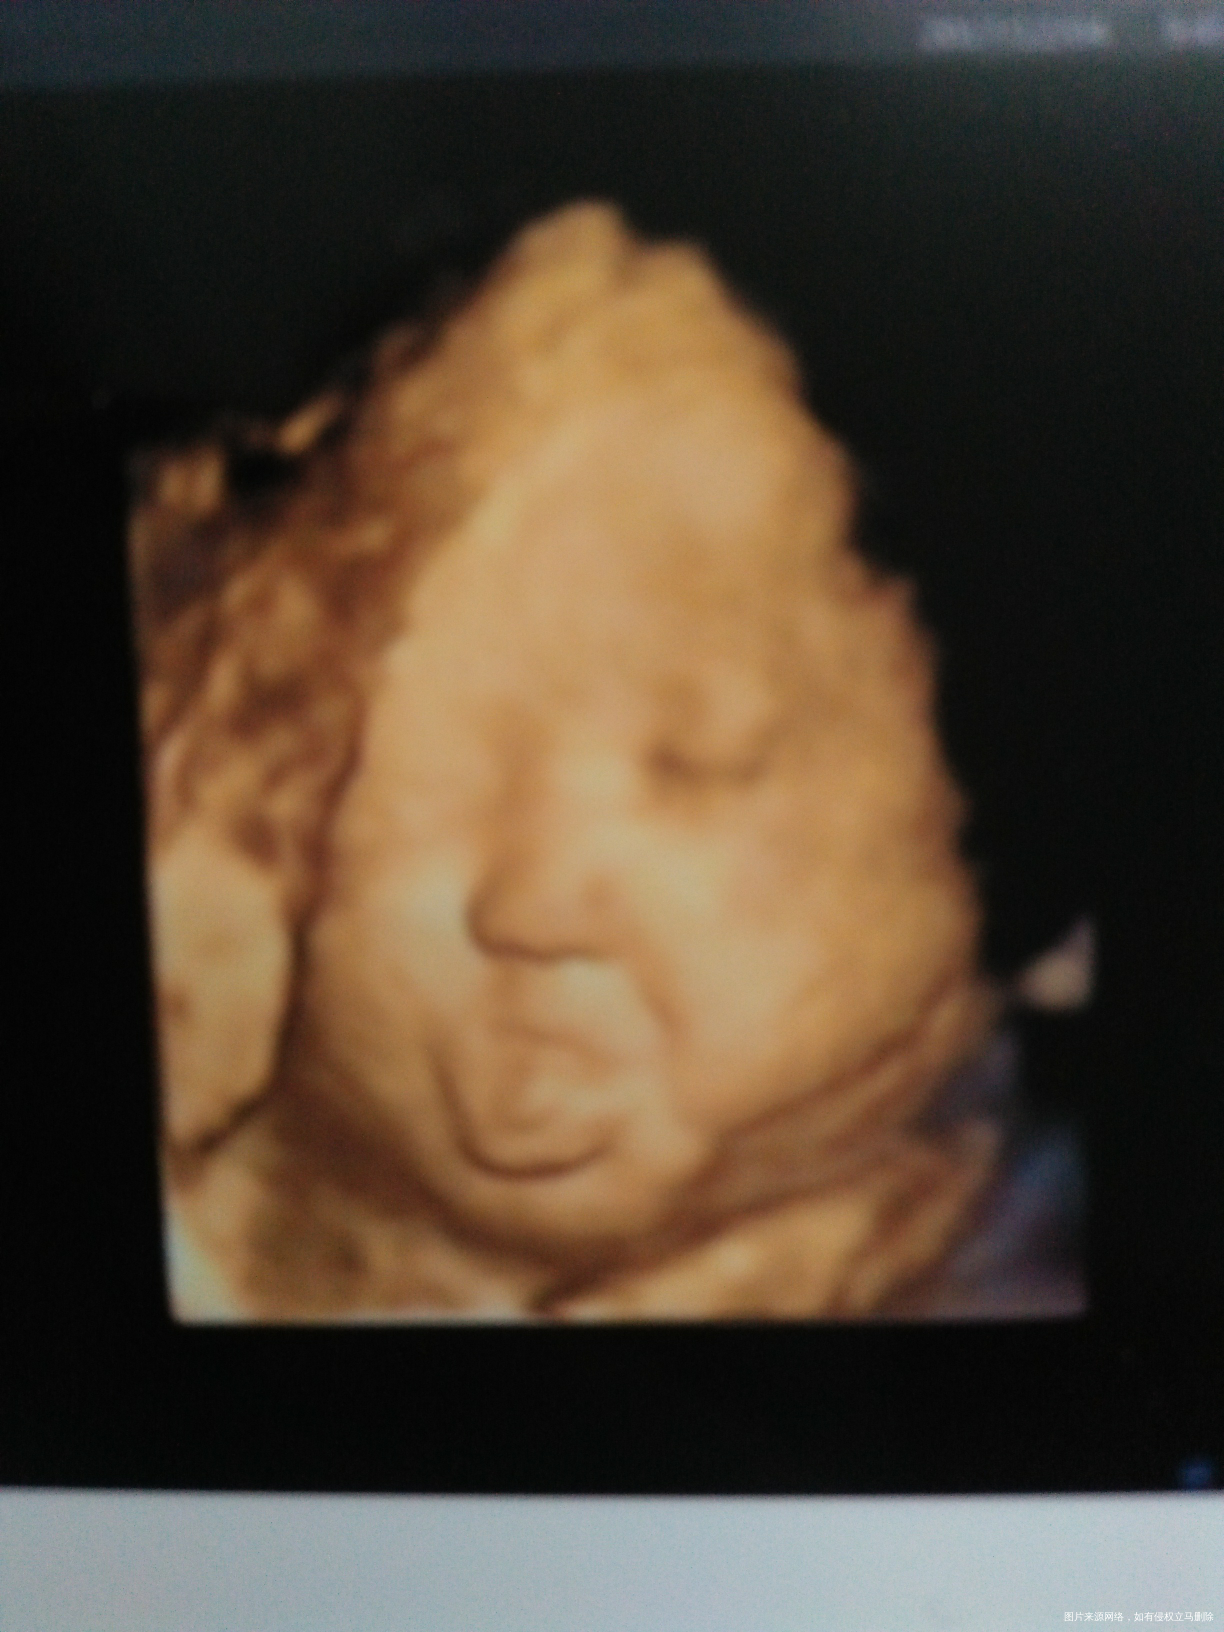

今天照四维,拍到崽崽吐舌头的照片,给姐妹们分享下,虽然其他部位不是很清晰,但我还是决定留下这值得纪念的一刻[大笑][大笑][大笑]